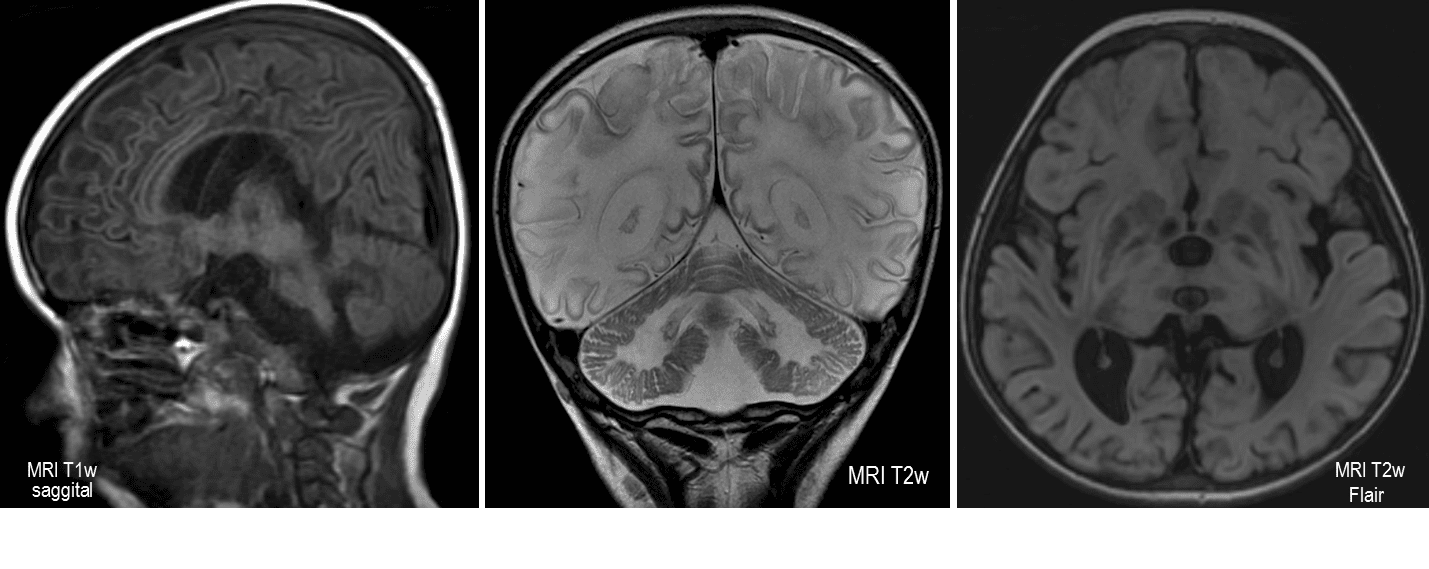

Progressive deterioration of nerve cells, and of mental and physical abilities, which commences, or starts, around six months of age and usually results in death by age four.

Occurs when harmful quantities of membrane components, known as gangliosides, accumulate in the brain's nerve cells, eventually leading to the premature death of the cells.